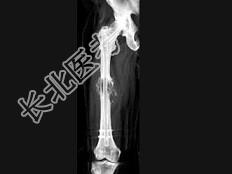

- 单项选择题男,18岁, 右股骨肿瘤术后,出现大腿中段疼痛, 夜间尤甚,结合CT图像, 最可能的诊断是 ( )